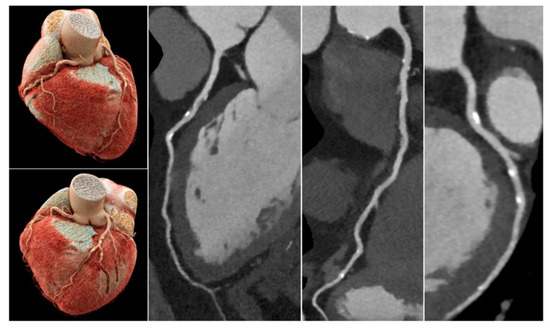

- Sun, Z.; Ng, C.K.C.; Wong, Y.H.; Yeong, C.H. 3D-printed coronary plaques to simulate high calcification in the coronary arteries for investigation of blooming artifacts. Biomolecules 2021, 11, 1307. [Google Scholar] [CrossRef]